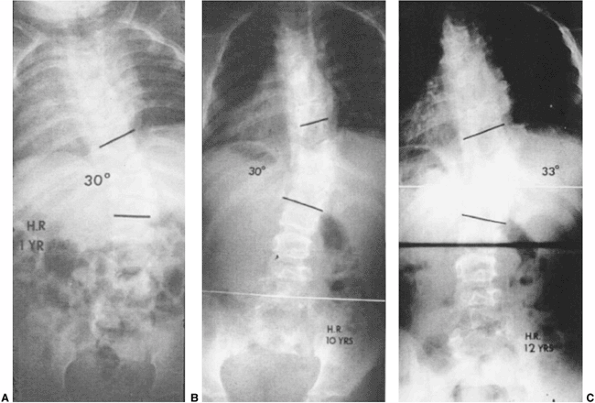

Figure 19.9 Relentless progression of untreated thoracic congenital scoliosis from 4 months of age (A) to 4 years of age (B) to 12 years of age (C).

Progression has occurred in the area of an unsegmented bar (segmentation defect) opposite hemivertebrae, with fused ribs in the concavity of the curve. |

Figure 19.12 Some extensive congenital anomalies are either not progressive or only minimally progressive. A: Fully segmented hemivertebrae with concave rib fusions and other anomalies are noted at 1 year of age. B:

The patient was put under observation only, and no treatment was given. No significant progression has occurred by 10 years of age. C: At 12 years of age after preadolescent growth acceleration there has been slight progression. No treatment was needed. |